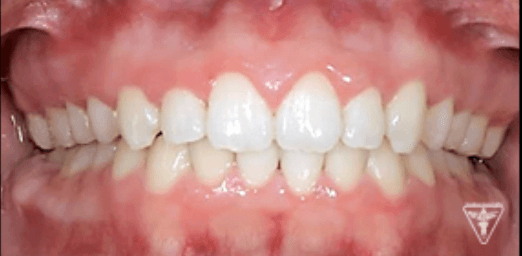

治療後

治療前後の比較